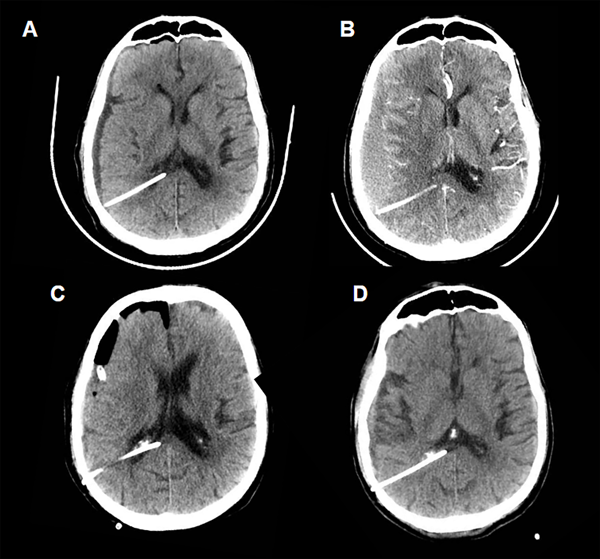

Caso 1 (Fig. 3)

Paciente masculino de 75 años de edad, que consulta por mareos, inestabilidad en la marcha e incontinencia urinaria. Se realizó RMN y TC donde se evidencia voluminoso meningioma petroclival izquierdo asociado a hidrocefalia obstructiva. Se decidió colocar una VDVP Codman Certas(R) a 150 mmH20. En la TC de cerebro control a las 48 hs postoperatorias se evidenciaba pequeño higroma derecho por lo que se aumenta la presión valvular a 170 mmH20 (Fig. 3A). Mantuvo controles periódicos, con crecimiento progresivo de dicha colección y aumento de la presión valvular hasta 200 mmH20. A los 2 meses postoperatorios, en contexto de crisis convulsiva, se realizó nueva imagen donde se constata el desarrollo de un voluminoso hematoma subdural (Fig. 3B). Se realizó la evacuación quirúrgica del mismo sin intercurrencias (Fig 3C). El paciente actualmente presenta estabilidad clínica e imagenológica, manteniendo la presión valvular en 200 mmH20, con un seguimiento sin nuevas intercurrencias de 19 meses (Fig. 3D).

Figura 3. Caso 1.

Fig A. Tomografía de cerebro control realizada a las 48 hs postoperatorias. Por evidencia de higroma se aumenta la presión valvular de 150 mmH20 a 170 mmH20, con posterior egreso sanatorial. Fig. B. TC de cerebro a los 2 meses postoperatorios, donde se evidencia hematoma subdural frontoparietal derecho subagudo (VDVP a 200 mmH20). Fig. C. Control realizado en el postoperatorio inmediato de la evacuación de dicho hematoma, se evidencia cavidad quirúrgica con drenaje subdural. Fig. D. Tomografía realizada al último control, sin signos de complicaciones.